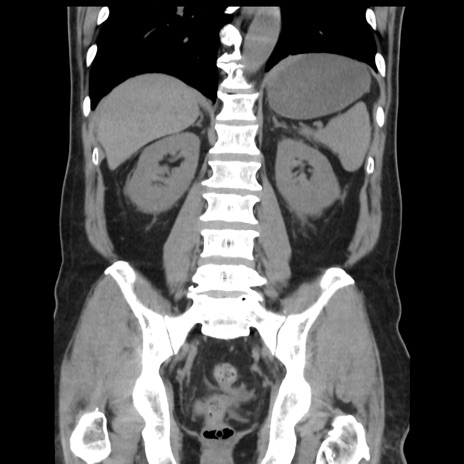

症例16(冠状断像)

【症例】 70歳代男性

【主訴】 腹痛、嘔吐

【現病歴】 約1ヶ月前より間欠的に腹痛と嘔吐あり、当院消化器内科を受診したところCTで多発する肝臓のLDAを指摘され、精査中であった。以降は消化器症状は安定していたが、2日前より嘔気と腹痛があり、同日より排便・排ガスが消失した。改善認めず、 本日、救急外来を受診した。

【既往歴】 大腸ポリープ切除後。

【身体所見】意識清明・会話良好、BT 36.3℃、BP 127/80mmHg、 P 80bpm、腹部:膨満あり、平坦・軟、上腹部正中および下腹部正中に圧痛あり、反跳痛なし、筋性防御なし。

【データ】WBC 7200、CRP 0.77